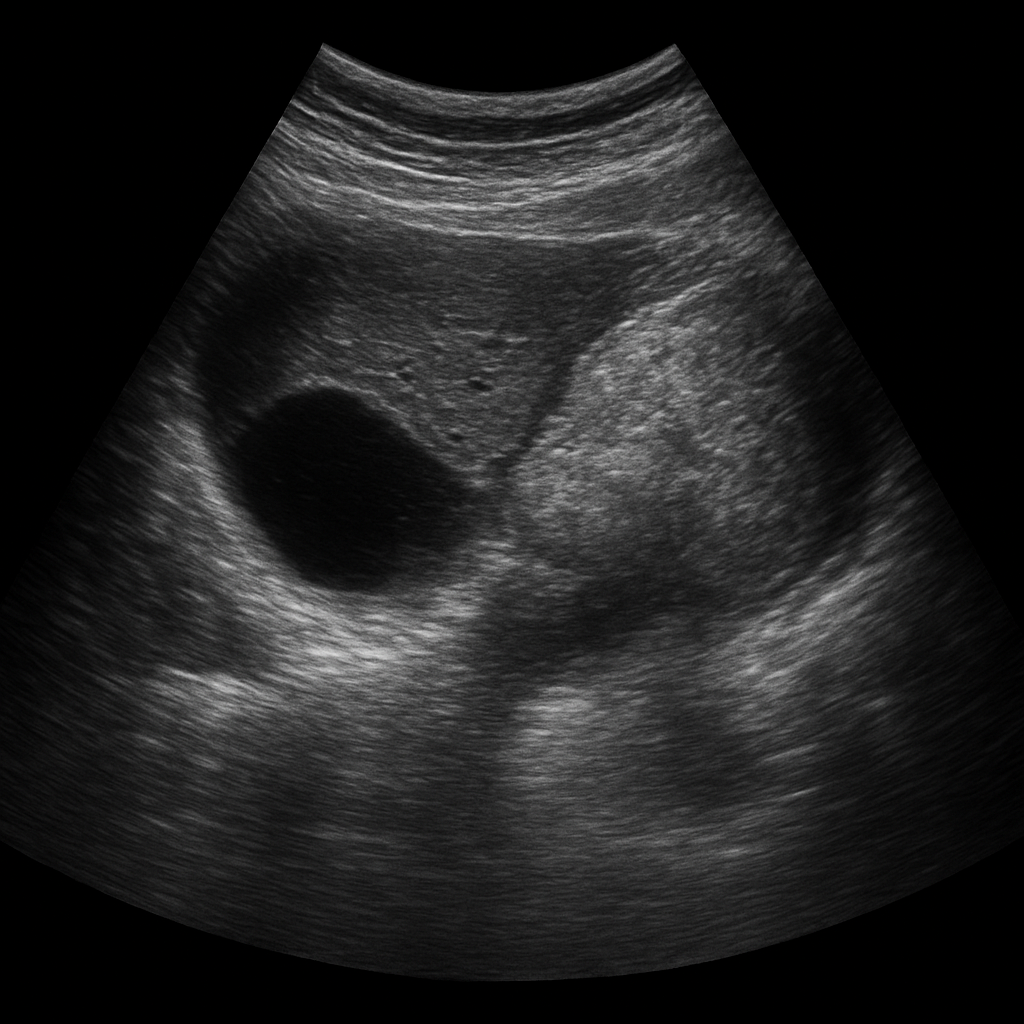

L’échographie abdominale repose sur l’émission d’ondes ultrasonores à haute fréquence à travers une sonde, appliquée sur la peau. Ces ondes se propagent à travers les tissus et sont réfléchies différemment selon la nature des structures qu’elles rencontrent (liquide, tissu dense, gaz, os). Le signal de retour est interprété par un logiciel informatique qui crée des images en temps réel.

Le radiologue, ou le médecin échographiste, peut ainsi observer l’aspect des organes, rechercher des anomalies morphologiques, mesurer des structures et, dans certains cas, guider des gestes diagnostiques ou thérapeutiques.

5. La rate

La rate est analysée en cas de suspicion de splénomégalie, d’anomalie hématologique, ou après un traumatisme abdominal. Des lésions bénignes ou malignes peuvent y être détectées.

6. L'aorte abdominale

L’échographie permet de mesurer le diamètre de l’aorte et de détecter une éventuelle dilatation anévrismale. Elle est essentielle dans le dépistage de l’anévrisme de l’aorte abdominale.